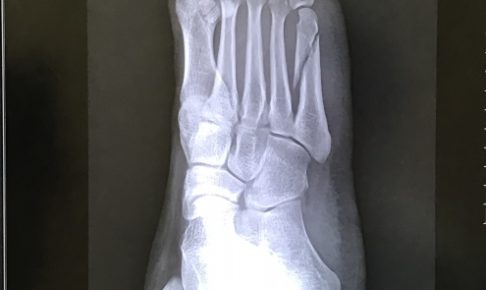

怪我ここ約1ヶ月疲労骨折でテニスの練習がまともにできませんでした。 痛みがひどい時には普通に歩くことも辛くて足を引…

怪我先日テニスの練習中フォアに振られたボールを打ち、カバーリングしようと右足を踏ん張った際、足首に「ピキッ」と刺激…